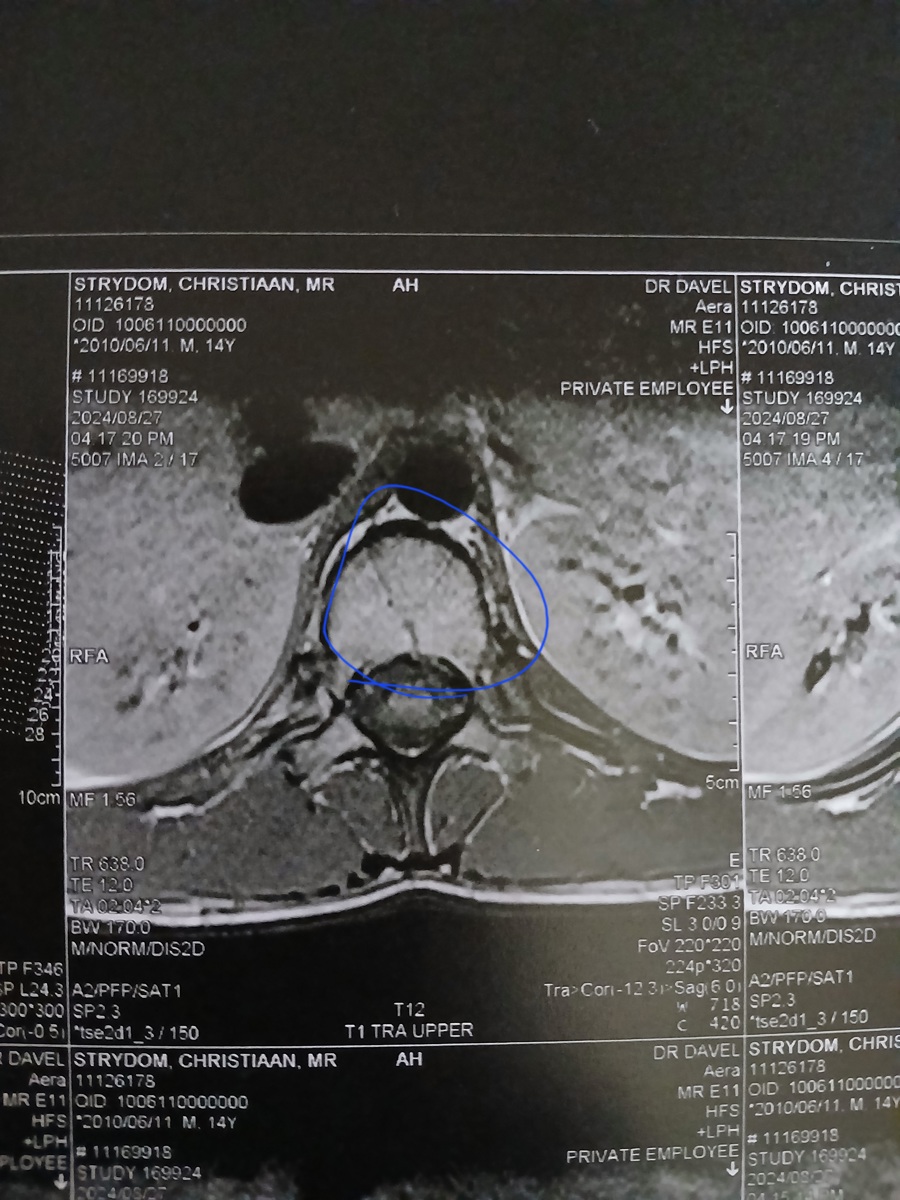

My seun Christiaan Strydom is 14 jaar oud en het die 20ste Julie 2024 ‘n beseering in ’n rugby wedstryd op gedoen. Hy het 3 van sy werwels gebreek en gekraak. Dit is sy T12, L4 en L1. Sy T12 is die ernstig gebreek maar alles is darem nog in plek wat baie goed is. Hy kry van die voorval sukkel oomblike as hy lank reg op sit of vêr of baie loop dan begin sy liggaam onbeheerlik te ruk. En dan is hy in vreeslik baie pyn en hy kan deesdae nie sy hande gebruik of loop dan nie. Hy het nog die krag in sy bene maar hy kan dit nie optel om te loop nie. Dit het in die begin so een keer ‘n week gebeur, maar die laaste twee weke gebeur dit een keer ’n dag. En dit is as of die gevoel in sy bene al hoe langer vat om reg te kom. Hy was tot vandag (12/09/2024) deur die Neurochirug dokters gesien en behandel by die Polokwane Provinsiale Hospitaal. Hulle het ons vandag verwys na die Spinale Ortopediese dokters toe wat ons eers die 1st Oktober ‘n afspraak by gekry het. Omdat ek nie ’n SASSA kaart het nie moet ons elke keer as hy hospitaal toe gaan om dokters te sien R350 betaal. Ons kon tans nie daar...